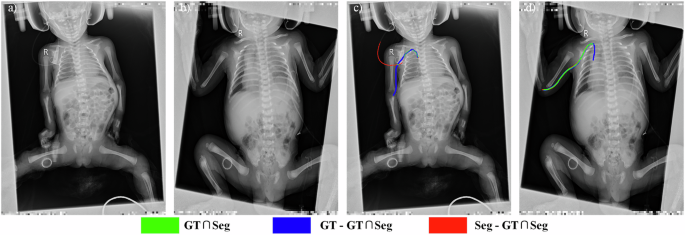

Upper extremity PICC segmentation: Fig. 2 shows an original image and corresponding segmentation results for a representative pediatric upper extremity PICC radiograph from Center I, as yielded by DFANet, FSNet, MDANet, MISSFormer, RSF-Conv, UNet++, and TopNet. Within these segmentation overlays, green indicates correctly identified PICC regions (true positives), red corresponds to false detections, and blue highlights missed target areas (false negatives). Compared to standard adult chest X-rays, the pediatric radiograph in Fig. 2a is slightly tilted and exhibits substantial occlusions, particularly along the right and inferior regions, which significantly complicate PICC detection. The thin structure of the PICC and its frequent overlap with bony structures make complete segmentation challenging. For example, discontinuous segmentation manifests as gaps within green areas, as seen in (b). Incomplete segmentation is evident in (c), (d), and (g), with model (g) failing entirely to identify the PICC. False positives (red regions) are present in (c), (f), and (h). Notably, these erroneous detections in (c) and (f) occur near the PICC tip, while those in (h) are mainly localized to the right side of the catheter. These observations underscore the superiority of TopNet over baseline models.

a Original upper extremity PICC radiograph from an infant / toddler from Center I. b–h Segmentation results obtained using different methods: DFANet, FSNet, MDANet, MISSFormer, RSF-Conv, UNet++, and TopNet (proposed). Green suggests correctly identified areas (correct detections), red denotes false detections, and blue marks undetected target regions (missed detections).